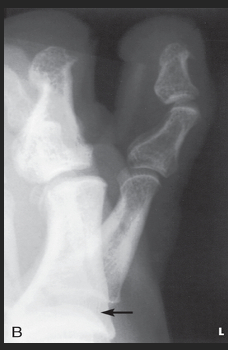

Name this projection.

AP oblique toes

State the degree and type of rotation used.

Medial rotation 30-45 degrees

Which aspect of the foot rests on the IR?

Medial aspect

Where does the CR enter?

Perpendicular to 3rd MTP joint

When radiographing the 1st-2nd toes, which oblique should be used?

Medial (rotate on medial/unaffected side)

When radiographing the 4th-5th toes, which oblique should be used?

Lateral (rotate on lateral/affected side)